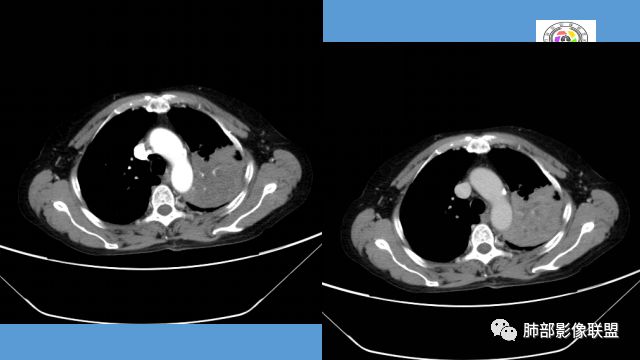

整个上叶尖后段阻塞性肺不张的表现,从强化来看没有异常结节状或肿块样强化,肿块内部点状钙化、纵隔多发小淋巴结、下叶背段有树芽征,整体来看支持肺结核,让人不放心的是最后一幅冠状位重建的图像尖后段支气管堵了,而且有轻度的隆起,所以很难除外粘液表皮样癌(女性,鳞癌可能性小),如果是我写报告肯定会建议纤支镜检查

中年女性,反复咳嗽咳痰4月,加重半月,咳嗽,咳黄痰。胸CT:左肺体积缩小,左肺上叶病变,病灶内可见支气管征,病灶边缘可见棘突样改变,病灶周围可见结节状卫星灶,纵隔可见淋巴结肿大,部分淋巴结可见钙化灶。增强CT病灶内可见低密度坏死区,冠状位病灶内支气管可见扩张,病灶整体呈收缩,考虑患者为良性慢性感染性病变,结核?放线?,建议支气管镜检查。

中年女性,反复咳嗽咳痰4月。胸CT:左肺上叶块状病变,病灶内可见支气管征,边缘见棘突样改变,周围可见结节状卫星灶,纵隔可见淋巴结肿大,部分淋巴结可见钙化灶。增强CT病灶内可见低密度坏死区。病灶整体呈收缩,考虑为良性病变,结核可能性大,建议支气管镜检查。

中年女性,咳嗽咳痰4月,加重半月。偶发热,肿瘤指标升高。病变主要位于左肺上叶后部,实变,病灶大部边缘平直、局部膨隆,邻近叶间裂局部向后膨隆,病变密度整体较均匀,见小斑片状低密度区及点状钙化影;左肺上叶舌段支气管可疑截断,病灶内支气管走形迂曲变形、不规则狭窄扩张、部分支气管内粘液栓形成,可见局部扩张支气管似小空洞相连,病灶内血管走形自然;糊墙。病灶前缘小叶间隔增厚,平滑;左肺下叶支气管管壁增厚,见部分树芽征及腺泡结节,边缘不清。纵膈及双肺门部分淋巴结钙化,隆突下淋巴结增大;未见胸腔积液。1.左肺上叶病灶倾向于恶性肿瘤,腺癌可能,排除粘液腺癌;2.左肺下叶少许炎症;

左上胸缩小,但是左上叶部分实变,边缘膨隆,内部有含气支气管,粘液栓,近端支气管堵塞

前端支气管通畅,部分稍扩张,走形自然

实变区支气管内粘液栓明显

病灶膨隆明显,支气管堵塞,附近壁增厚,是否需要警惕恶性?

腺癌?近端支气管壁增厚,病灶区占位效应明显,小叶间隔增厚,血管走形自然,不能排除  。

2.左肺上叶大片实变影,密度不均,体积轻度增大,注意轻到中度强化及血管影未见破坏、未见坏死空洞……病灶更符合炎症,而不大支持干酪性结核及肺鳞癌等,后两者的破坏能力是比较强的。

3.支气管阻塞,沿途可见钙化及液性潴留……更符合支气管内膜结核。

综上,双肺继发性肺结核诊断应当成立;左肺上叶大片影,以支气管内膜结核伴阻塞性炎症解释更为合理。